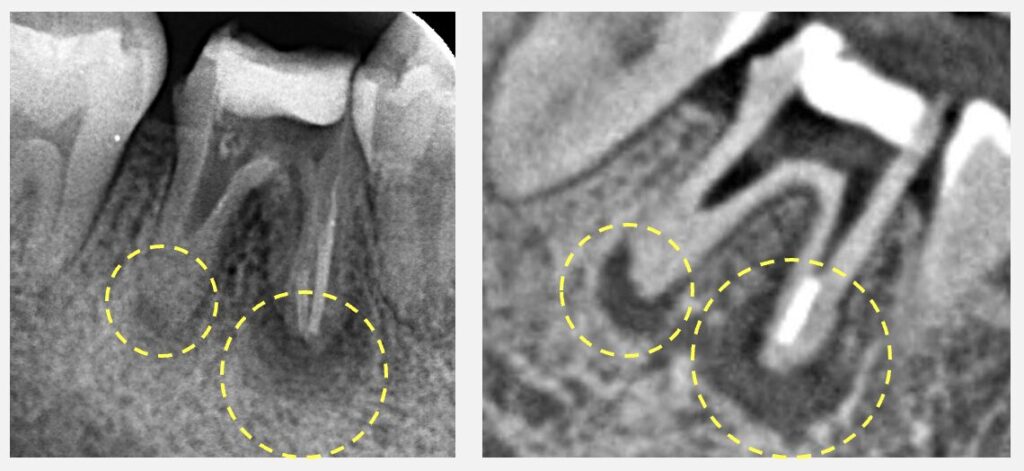

右下奥歯の痛みがあるため、2ヶ月前にかかりつけの歯科医院で根管治療を開始しました。複数回治療を受けましたが、痛みが引くどころか日に日に強くなり、不安になり当院を受診されました。受診前日には、あまりの激痛のため大学病院の夜間診療を受診していました。根尖性歯周炎の急性炎症に対する必要な処置について解説しています。

根管治療を続けていても痛みが引かない理由は様々ですが、根の問題のほとんどは根の中の細菌感染が原因です。つまり、治療を繰り返していても、根の中に細菌が残っていると治らないといえます。しかし、細菌というのは眼に見えるわけではないので、ラバーダムやマイクロスコープを使って、さらに虫歯もしっかり取り除いた上で、できる限り根の中をきれいにする、という処置が必要となります。